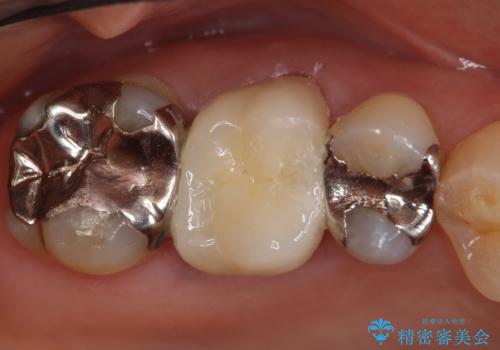

根管治療も希望されたため、再根管治療終了後、オールセラミッククラウンによる補綴を行いました。

今回用いたオールセラミッククラウンはジルコニアフレームという白い素材の上にセラミックを盛っているため、審美性が非常に高いのが特徴です。

また、ジルコニアは人工ダイヤモンドの材料にも使われているほど高い強度を持っており、そのためオールセラミッククラウンは審美性だけでなく、奥歯やブリッジの補綴も可能とするクラウンです。